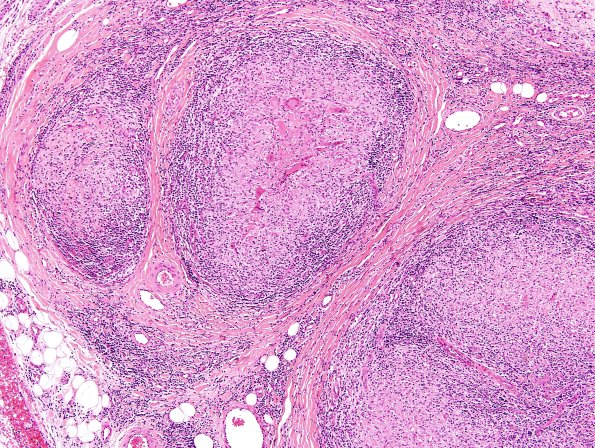

Washington University Experience | PERIPHERAL NEUROPATHY | 10 INFECTION | 4 Leprosy – Tuberculoid | 5A5 Leprosy, tuberculoid (Case 5) H&E 3

5A5,6 The central portion of each granuloma has a more complex structure in this case. (H&E)